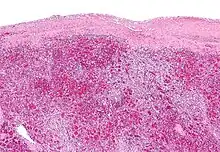

Pulp

| Area | Function | Composition |

| red pulp | Mechanical filtration of red blood cells. In mice: Reserve of monocytes[5] |

| white pulp | Active immune response through humoral and cell-mediated pathways. | Composed of nodules, called Malpighian corpuscles. These are composed of: